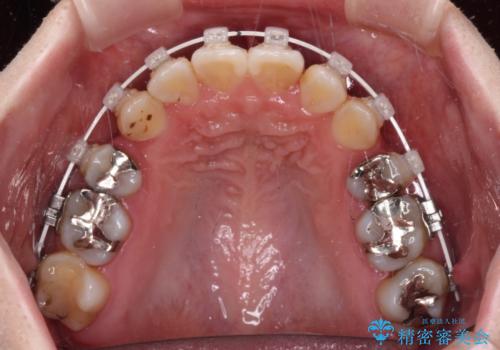

- 矯正装置

- インビザライン・審美装置

マウスピース(インビザライン)はほとんど使用することができませんでしたが、補助装置により上顎の八重歯は改善しておいたので、ワイヤー装置ではスムーズに治療を終えることができました。